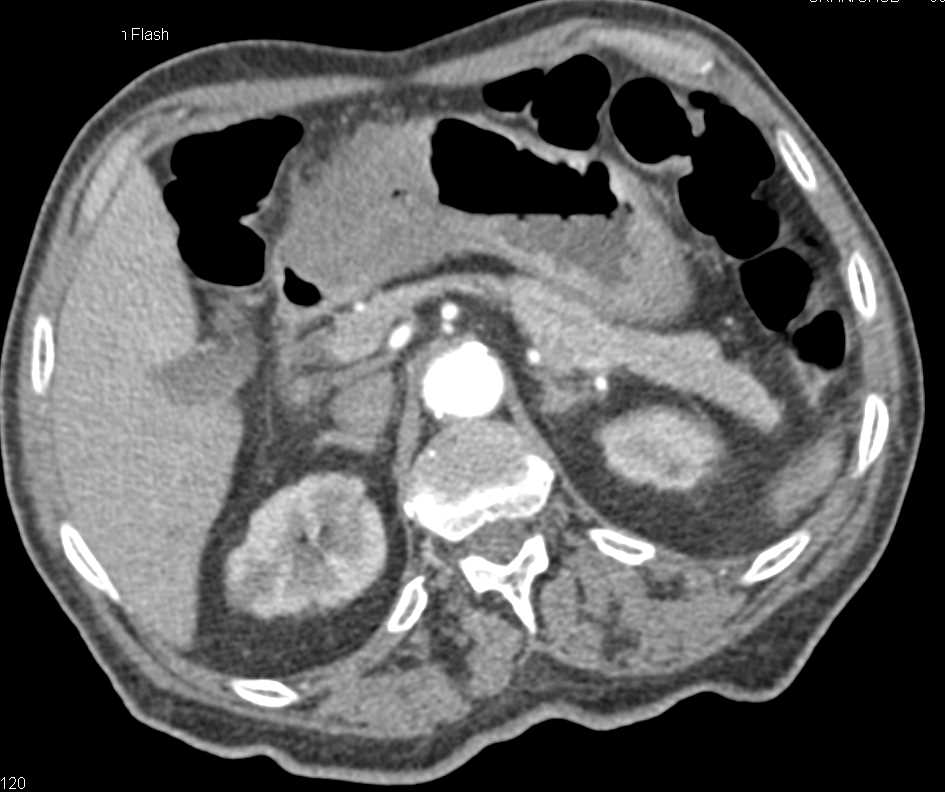

Gastric GIST Tumor